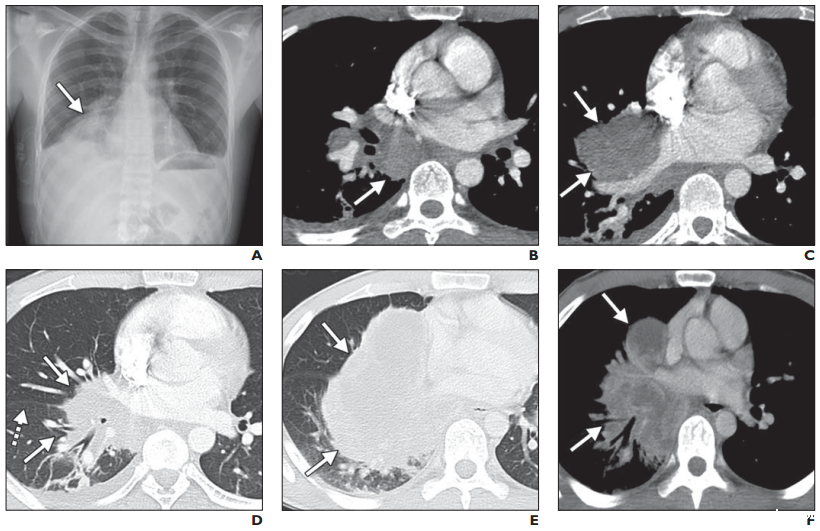

一名25岁男子出现进行性不断加重的气促伴发热等症状。

A图:

首次就诊的胸部X射线显示右侧肺门影增粗(箭头)。同时存在轻至中度右侧胸腔积液。

B-D图:

增强CT软组织窗(B和C)和肺窗(D)显示右下肺门肿块(实线箭头,B-D图),跨裂隙向右中叶和下叶扩展(虚线箭头,D图)。同时可见隆突下淋巴结肿大。

E图:

2周后再次行胸部CT:右侧肺门病灶及纵隔淋巴结体积较前显著增大(实性箭头),肿块现在占据右侧中叶和下叶的大部分区域。